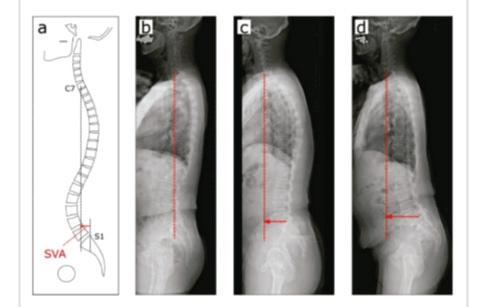

Cuando mires a tu postura desde un lado y observes una inclinación hacia delante, no la ignores

Cambios estéticos en tu postura a medida que te haces mayor

Nadie quiere hacerse mayor con la cabeza inclinada hacia delante o una chepa en mitad de la espalda. El estado de tu postura influye y mucho en tu aspecto físico, estado emocional y autoconfianza. Además, a medida que envejecemos, la columna tiende a curvarse más. Si mantienes un programa básico de higiene de la columna y tus ajustes con el quiropráctico, el proceso de envejecimiento puede ser considerablemente más lento.

En un nuevo estudio, se ha demostrado que una postura inclinada hacia delante en los pacientes que no padecen alzhéimer indica un rápido deterioro de la función cognitiva. Solo porque estés envejeciendo, no significa que tengas que soportar dolor y un mal funcionamiento cerebral. Un pequeño cambio porcentual en la simetría de la postura de una persona de edad avanzada le ofrece mucho más bienestar con su cuerpo. Es verdad que no volverá a tener 16 años, pero los pequeños cambios progresivos pueden ayudar sorprendentemente bien.